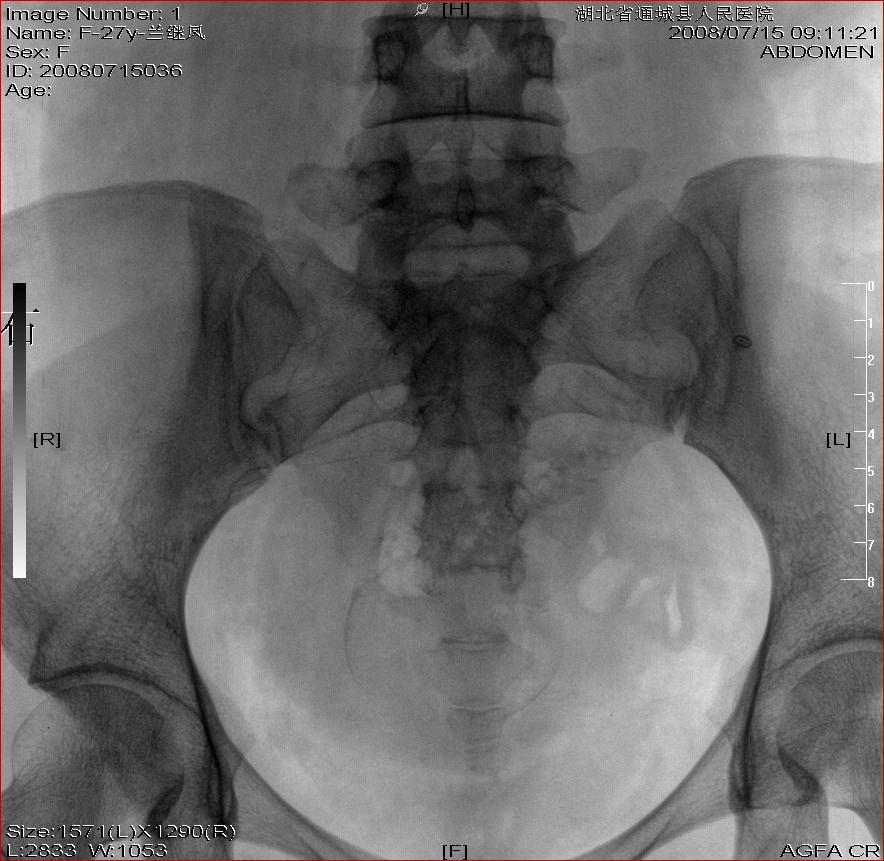

标题: X4684左肾结石+腹部胎儿

左肾结石+腹部胎儿

b超示双肾结石。孕妇及家人签字画押弃胎治石。才行平片检查,结果结石如此小。